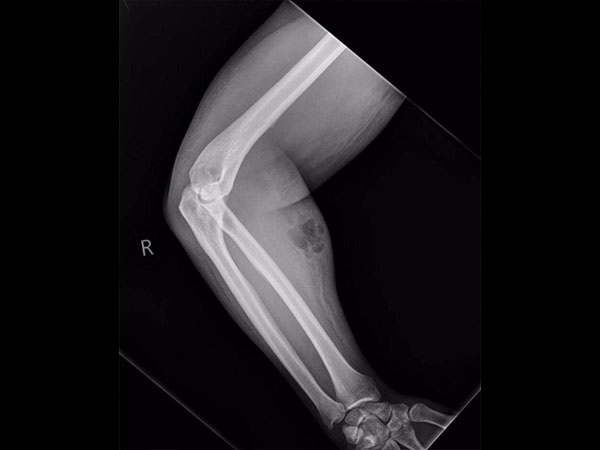

Khi nghe vậy, các bác sĩ đều choáng váng và càng không thể tưởng tượng được là người đàn ông này đã tự tiêm tinh dịch suốt 18 tháng để tự điều trị chứng đau lưng liên tục của mình. Các bác sĩ đã chụp X-quang cánh tay đang bị sưng và phát hiện tinh dịch đã rò rỉ vào mô mềm, gây ra nhiễm trùng.